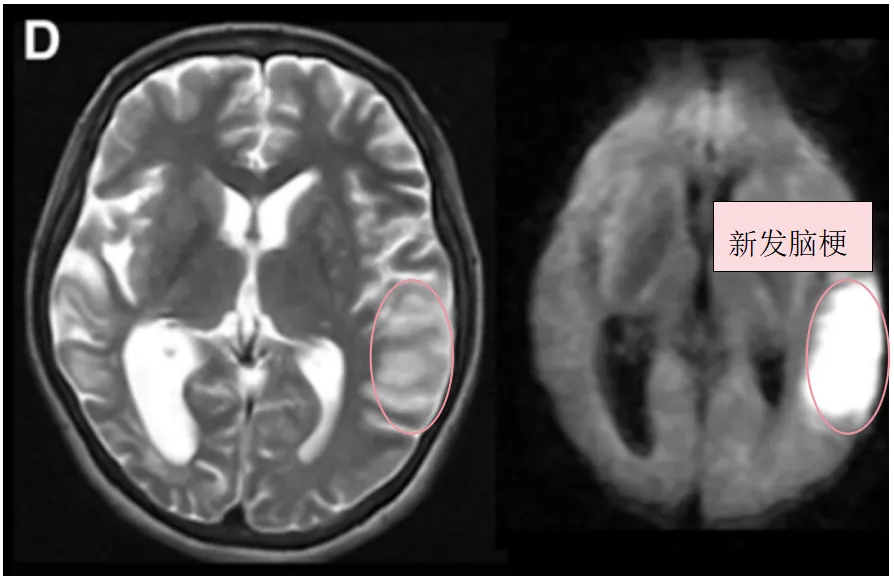

确诊后一个月,小玉因构音障碍和右腿无力再次入院。MRI检查结果令人揪心:她左额叶出现了新的脑梗死灶。

然而灾难并未停止。入院三天后,影像检查显示她左侧颞叶再次出现新发脑梗死。一次又一次的打击,让小玉的神经功能迅速衰退,MRS评分达到4分——重度残疾。

图C:术前T2、DWI序列显示左额叶新发展的脑梗死

图D:入院3天后术前T2、DWI序列显示左侧颞叶进一步新发脑梗死